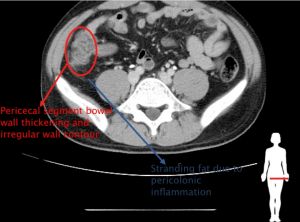

電腦斷層為優先考量,可能發現腸道變厚(wall thickening),周邊腸系膜脂肪的成股相紋(stranding),結腸憩室(Diverticula)。嚴重者可能會發現瘺管(fistula)或是腫瘍(abscess)。